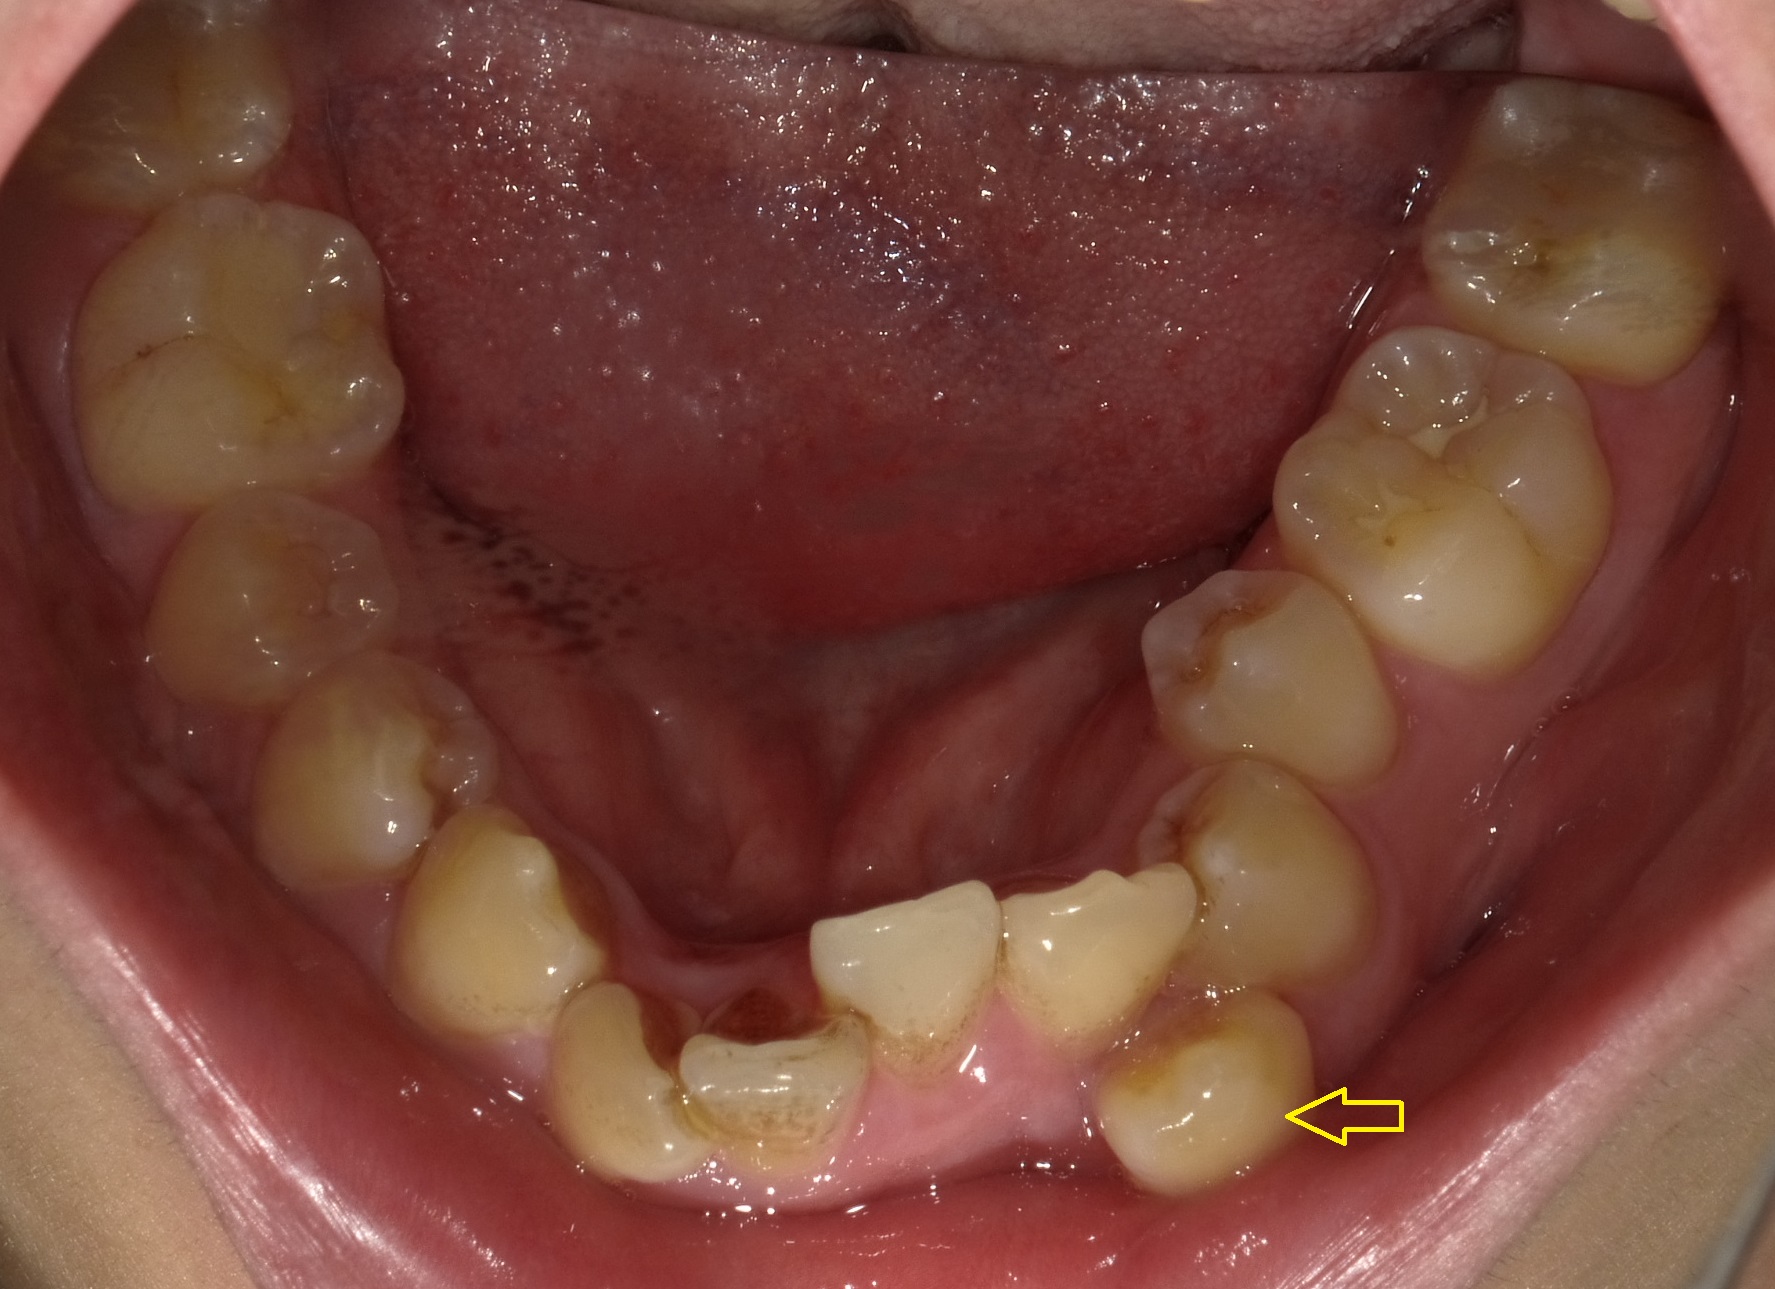

次に下の歯並びです。なんかもう色々大変です、笑

特に左下の犬歯が大きく列からはみ出し(おそらく生える順番が著しく遅かったからだと思われます)

特記すべき点としては、特に下顎は奥歯が全て内側に傾斜していて、噛み合わせが深くなっています。

歯並びに目が行きがちですが上下の前歯のかみ合わせに注目すると、上の歯が下の歯をほぼ隠すくらいに噛みこみがおこっています。

現状ではほぼ抜歯は必要と思われますが、まずはこの噛み合わせの深さをある程度改善してから抜歯・非抜歯を決断していきます。